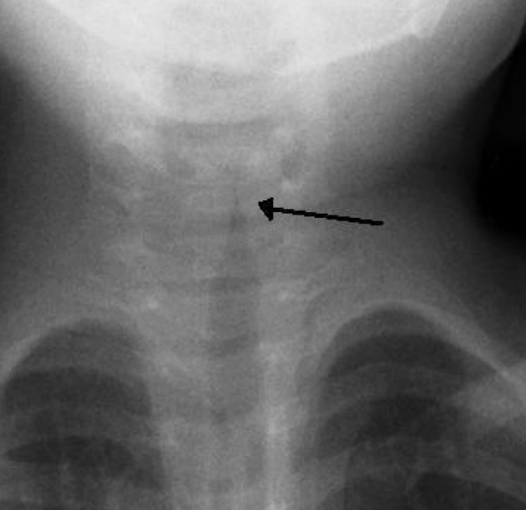

dx of CROUP

- neck/chest xray for steeple sign (narrowing of the airway)

- tx is symptomatic and it should be carefully selected to avoid airway obstruction

- when this is present, we can start seeing the STEEPLE sign in x-rays (narrowing of the airway)